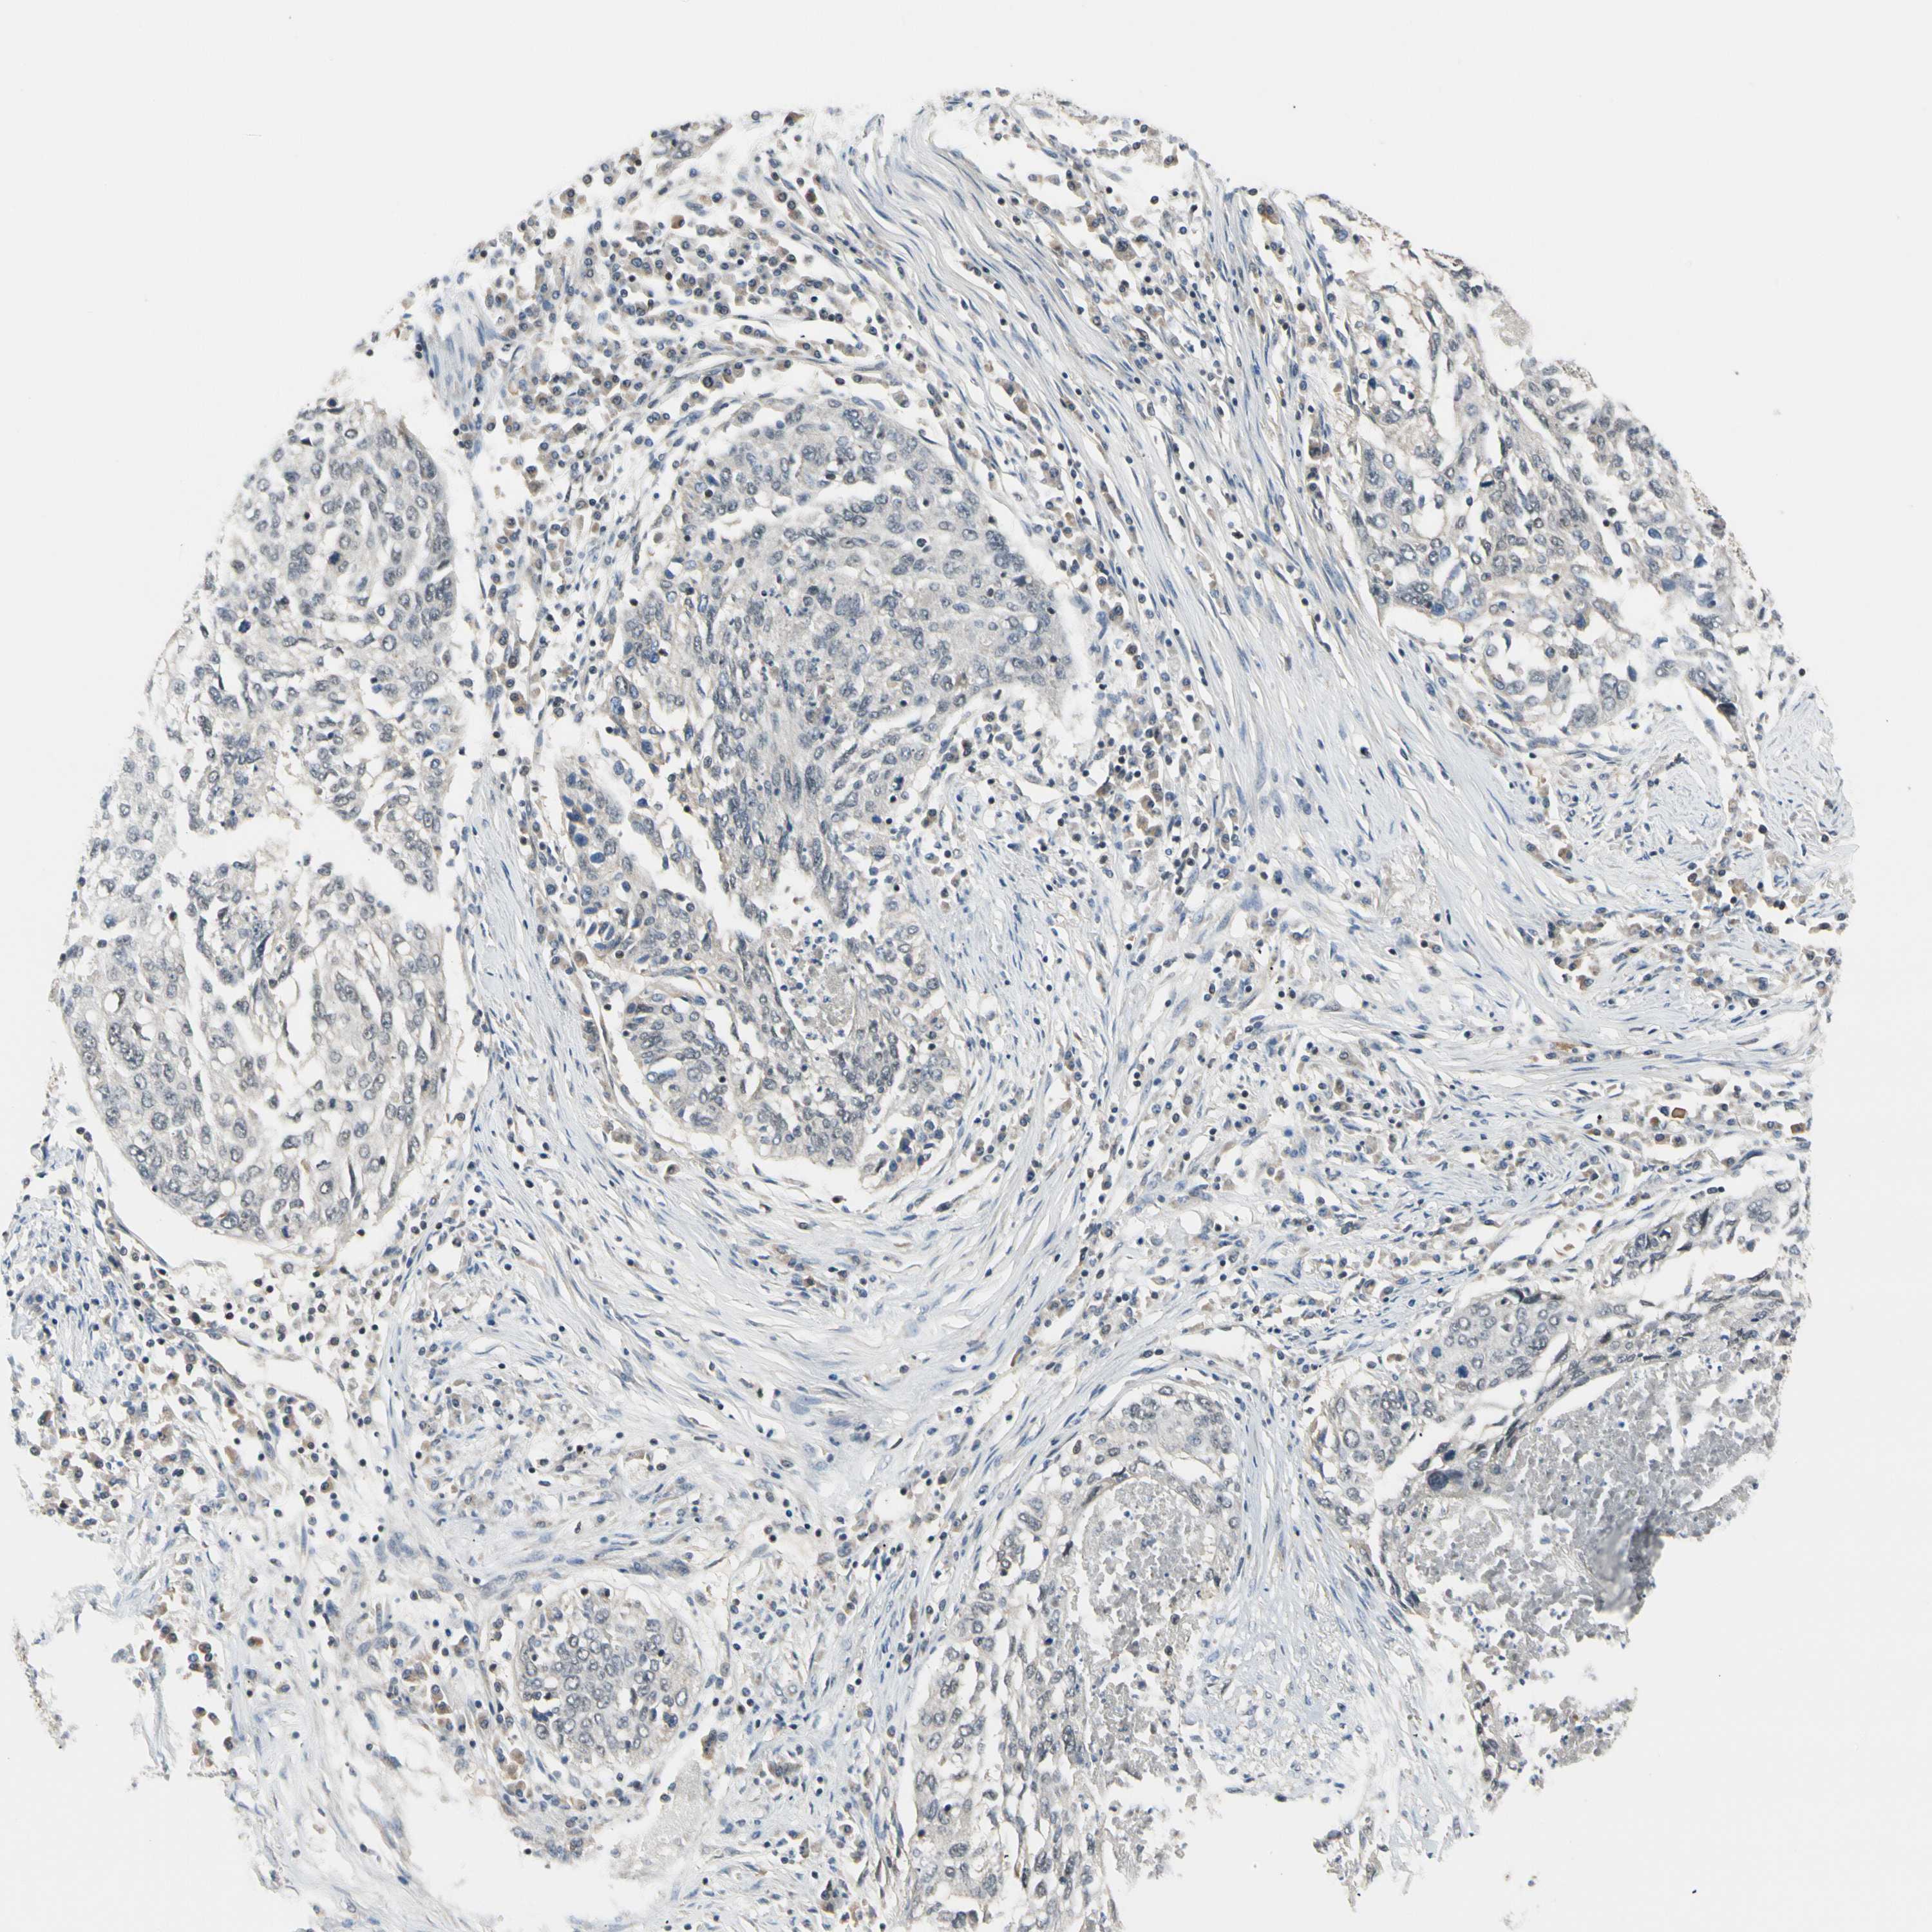

TAF12